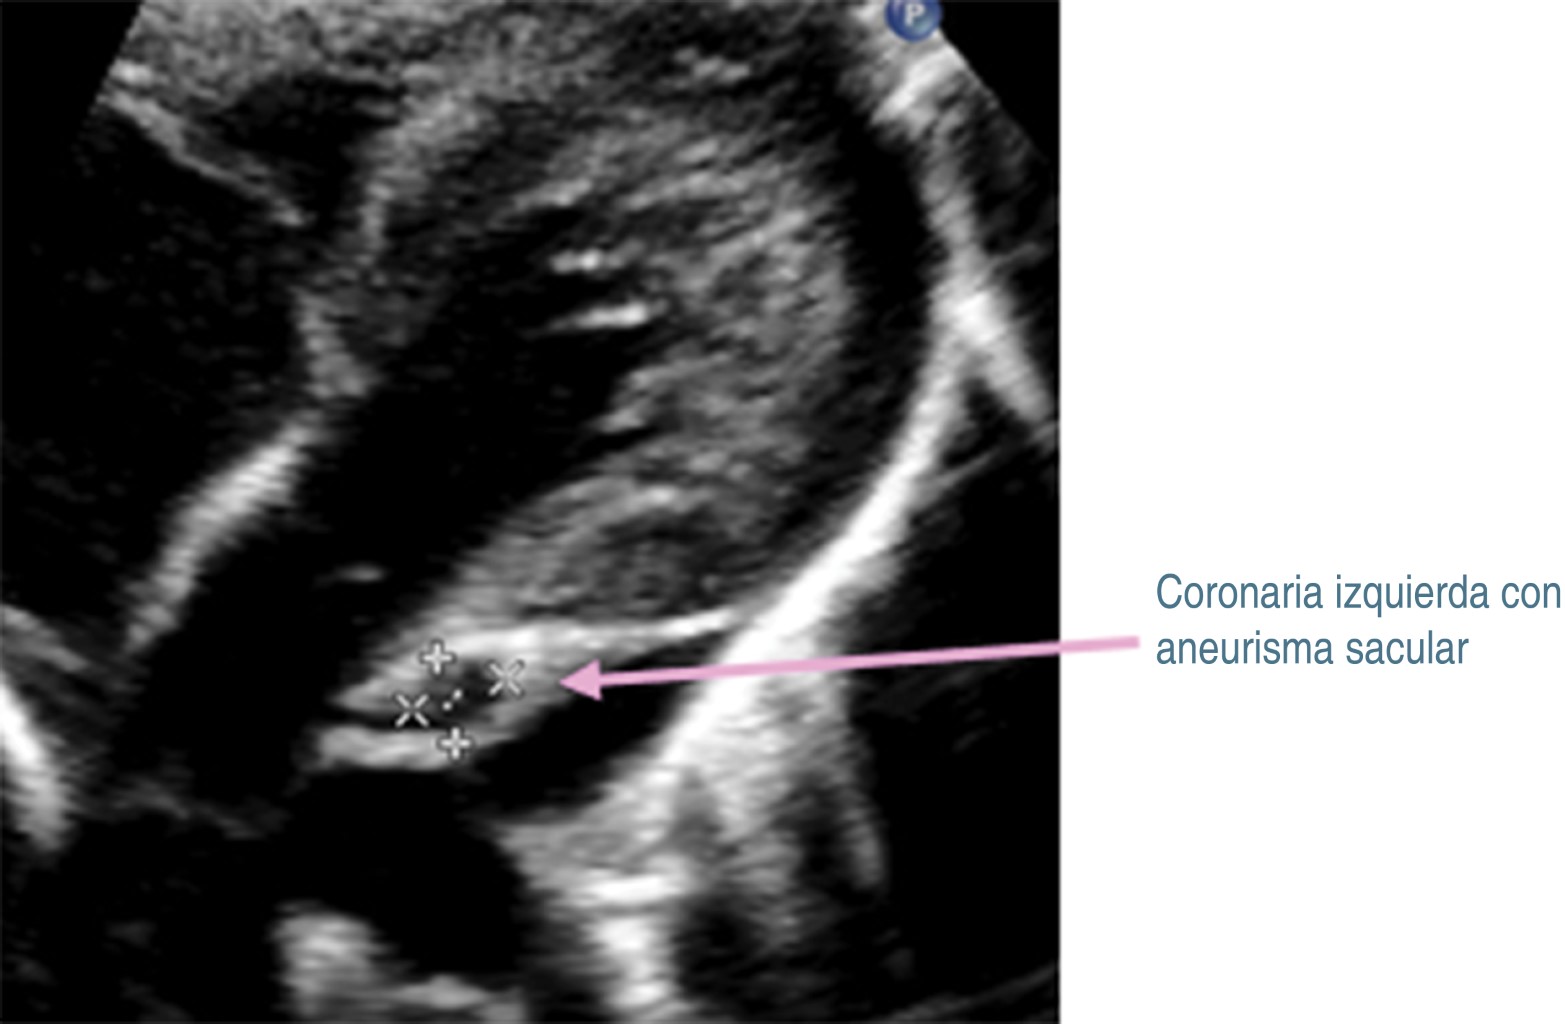

Tras 30 días del padecimiento y por la persistencia de la fiebre, se decide traslado a nuestro hospital. A su ingreso se corrobora fiebre, se ausculta soplo cardiaco holosistólico en mesocardio grado II/VI y soplo sistólico regurgitante en foco tricuspídeo grado II/VI, pero sin repercusión hemodinámica. Se decide continuar con antibióticos, iniciando protocolo de estudio de fiebre de origen a determinar. En nuevos exámenes de laboratorio (Tabla 1, columna B), se determina leucocitosis, neutrofilia, trombocitosis e hipoalbuminemia. Radiografía de tórax, ultrasonido abdominal y tomografía computarizada de cráneo fueron normales. En electrocardiograma se observó crecimiento de cavidades izquierdas, sospechando endocarditis, por lo que se realiza ecocardiograma transtorácico (ECT), con los siguientes hallazgos: persistencia de conducto arterioso; en arteria coronaria izquierda (Figura 1) se observa aneurisma sacular que mide 4.6 mm de ancho y 5.2 mm de longitud (z-score +9.2), así como imagen sugestiva de trombo en su interior. En coronaria derecha (Figura 2), origen: 4.2 mm (z-score +8.6), se observan dos aneurismas fusiformes en la porción proximal, uno mide 9.9 × 53.9 mm (z-score + 7.7), y otro más en la porción distal que mide 7.6 × 3.2 mm (z-score +7.1). Además, se detectó derrame pericárdico laminar y función sistólica ventricular conservada.

Los datos previos orientaron a que se trataba de EK, por lo que se inicia inmunoglobulina intravenosa (IGIV) humana a dosis de 2 g/kg/día, ácido acetilsalicílico (ASA) a dosis de 80 mg/kg/día, clopidogrel (0.5 mg/kg/día) y enoxaparina (1 mg/kg/dosis). La fiebre cede en las primeras 24 horas, presentando mejoría del estado general. Cinco días después, en ECT de control, el tronco coronario izquierdo medía 3.9 mm (z-score +7.05), sin evidencia de trombo en su interior. Mientras que en la coronaria derecha hay regresión de aneurismas fusiformes a aneurismas pequeños, midiendo 2.4 × 5.4 mm en porción proximal (z-score + 3.16), y de 1.9 × 4.5 mm en porción distal (z-score + 2.75) (Figura 3). En el tronco coronario izquierdo medía de 3.9 (z-score + 7.05), sin evidencia de trombo (Figura 4).

Figura 1